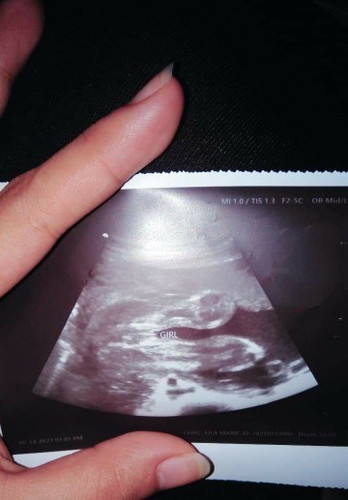

ULTRASOUND

sure na po ba girl?? 6months po ako nagpa ultrasound.

Yes, girl mommy. (Three lines and hamburger sign) Congratulations! ❤

Ultrasound 6months